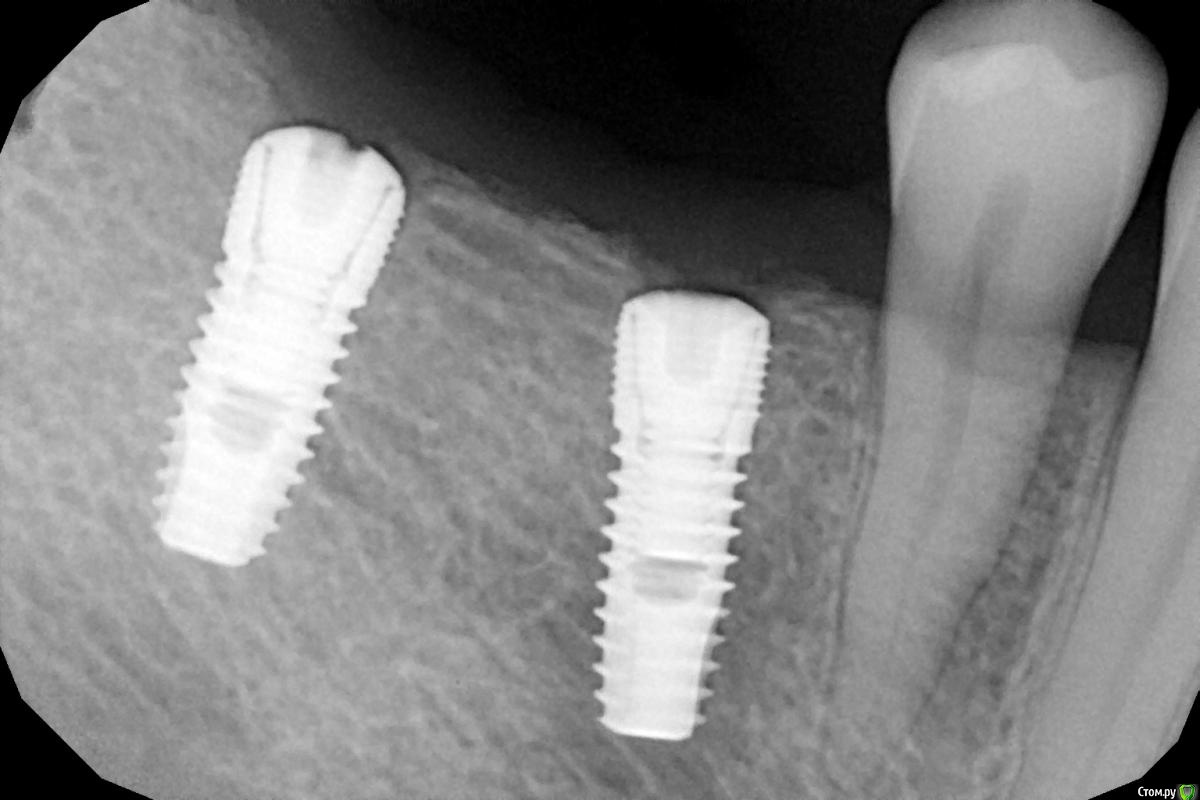

Женька Опубликовано 28 ноября, 2020 Поделиться Опубликовано 28 ноября, 2020 (изменено) Приветствую коллеги. В общем три недели назад 07.11.20 установил пациентке 2 имплантата в позиции 45-46. Гребень по ширине был около 6.5мм в области 4.5 и около 7.2мм в области 4.6 (с учётом заглубления на 1.5-2мм). Это была наверное первая имплантация во время которой я чувствовал себя спокойно и расслабленно. Всё прошло хорошо, немного покопался с непосредственным введением имплантатов, тк никак не хотели топиться на нужные 1.5мм. Поэтому пробовал методику с выкручиванием на пару витков и снова закручиванием. Особого толку не получил, потому взял финальную фрезу и чуть углублял ложе. Так несколько раз, тк боялся всё-таки немного что задену менталис и нлн. Ввиду того, что биотип у пациентки тончайший и язычно было совсем-совсем тонко - заглушки и швы. Назначил нпвс, ванны хг, аб терапию. Но на утро следующего дня пациентка сказала, что чувствует себя шикарно, решили что нпвс оставим, а аб терапию применять не будем (и грешу что в этом мою ошибка).Через неделю сняли швы, всё отлично.Спустя два дня после снятия начались какие-то "костные" боли, как говорит пациентка в области 4.5 импланта. Которые то отпускают, то снова наплывают. На 4.4 есть дефект твердых тканей (на фото виден), но судя по всему беспокоит не он .Пальпация вестибулярно в проекции 4.5 импланта болезненна, небольшая гиперемия, отёка нет. Гигиену пациентка запустила, тк боялась туда залезать и чистить. Снимки прилагаю первые два от 07.11, два последующих 28.11. Ну и внутри ротовые день операции и сегодняшние числа.Похоже 4.5 на выход? своими "туда-сюда" наверняка я нагрел всё что можно... снова расстройство в той работе, где накосячить предельно сложно... Добавка: пить аб ведь сейчас уже бесполезно? Изменено 28 ноября, 2020 пользователем Женька Ссылка на комментарий

Женька Опубликовано 28 ноября, 2020 Автор Поделиться Опубликовано 28 ноября, 2020 (изменено) Какой торк получили?45Вы тоже видите заглушки светят? Изменено 28 ноября, 2020 пользователем Женька Ссылка на комментарий

колесников Опубликовано 28 ноября, 2020 Поделиться Опубликовано 28 ноября, 2020 (изменено) Имплант 13 мм? Зачем? При планировании видно, что он упирается апексом в кортикалку. По этому и поставить не могли сразу. Торк 45. Если имплант плотно контактирует с компактной пластинкой,она резорбируется окончато,со всеми вытекающими. Стоило выбрать имплант 8.5мм. Если притопили имплант,зачем поставили заглушку? Имплант зарастёт придётся выпиливать ,откапывать заглушку,ломать то что наросло непосильным трудом. Хороший торк-ставьте рабочий фдм. Сомнения-мелкий фдм или заглушка +1. Рекомендую сделать контрольный кт и поставить фдм Изменено 28 ноября, 2020 пользователем колесников 5 Ссылка на комментарий

Женька Опубликовано 29 ноября, 2020 Автор Поделиться Опубликовано 29 ноября, 2020 Я бы сейчас сделала три вещи :дала курс антибиотика шикарной женщине,гигиену навела бы во рту или хотя бы в этой области,депульпировала премоляр.Чтобы прикрыться со всех сторон. Выждать. Вынуть всегда успеется.А потом.. может,там уже формики просятся?Три недели, не рановато ли? По поводу премоляра, терапевта напрягу. А на каком режиме Вы закручиваете/выкручиваете?20оборотов на торке 30, далее руками динамометрическим ключом. Имплант 13 мм? Зачем? При планировании видно, что он упирается апексом в кортикалку. По этому и поставить не могли сразу. Торк 45. Если имплант плотно контактирует с компактной пластинкой,она резорбируется окончато,со всеми вытекающими. Стоило выбрать имплант 8.5мм.Импланты 10мм каждый, разметка на планировании - глубина препарирования с учётом заглубления. Проблема то как раз в области 4.5 импланта, там нет такого контакта с кортикой апикально, а область шейки хорошо развальцевал кортикальной фрезой. 4.6 где как раз контакт кортикальный спокоен. Если притопили имплант,зачем поставили заглушку? чтобы избежать проблем как в предыдущем моём случае, где тоже было тонко язычно. Потому хотел на этапе раскрытия работать с десной и язычно перемещать объём. http://forum.stom.ru/topic/40254-otsrochennaia-implantatciia/ Сомнения-мелкий фдм или заглушка +1. что значит заглушка +1? Если сейчас залезть и выкрутить заглушки не велики ли риски прокручивания имплантата...ведь на 3-5 недели самая большая потеря первичной стабильности происходит. Ссылка на комментарий